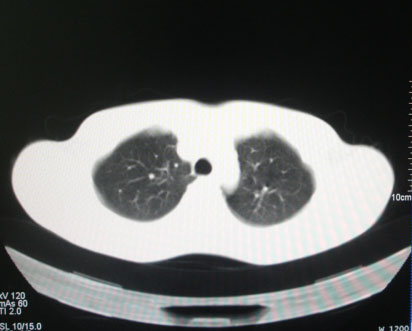

标题: CT26938:单发肺窗

病人17岁。咳嗽伴血丝痰2年?外院x片示左上肺椭圆形影,疑胸腺瘤

左肺尖见占位,建议上传纵隔窗及向上扫描。